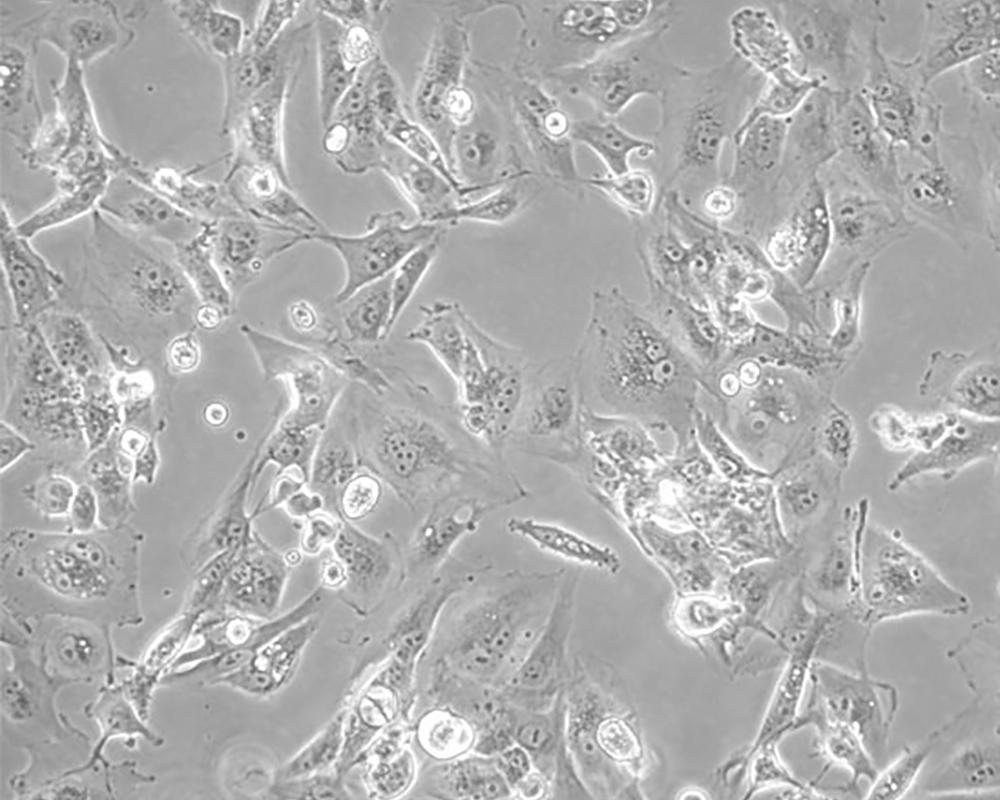

Caki-1

產品名稱 Caki-1

中文名稱 人腎透明細胞癌皮膚轉移細胞

組織來源 腎透明細胞癌;皮膚轉移;男性

生長特性 adherent

培養基 McCoy's 5A+10% FBS+1% P/S

形態特征 epithelial

細胞描述 該細胞超微結構中包含許多微絨毛、少許微絲、許多小線粒體、發達的高爾基休和內質網、許多脂滴和多層體、次級溶酶體,沒有發現病毒顆粒。